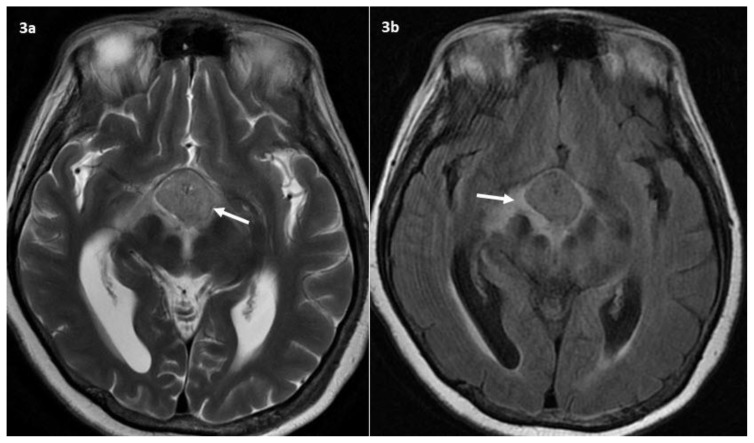

Figure 3.

59-year-old lady with clival chordoma.

Findings: Follow up MRI brain 1 month later. (a) Axial T2W image showed interval enlargement of the sellar/suprasellar mass. (b) Axial T2W FLAIR sequence shows new vasogenic edema around the mass. This is complicated by new acute obstructive hydrocephalus as evidenced by dilatation of the lateral ventricles with cerebrospinal fluid transependymal seepage seen as periventricular high signal.

Technique: 3T General Electric (GE) Discovery MRI scanner

a) Axial T2W. TR 4975. TE 102. 5mm slice thickness.

b) Axial T2W FLAIR. TR 9000. TE 152. 5mm slice thickness.

Biochemical tests revealed monomeric hyperprolactinemia, hypocortisolism, hypothyroidism and central diabetes insipidus. A follow-up MRI done a month later showed mild enlargement of the mass, measuring 2.3 × 2.4 × 4.2 cm, with compression of the third ventricle and foramen of Monro (fig. 3). This resulted in acute obstructive hydrocephalus with transependymal cerebrospinal fluid seepage.